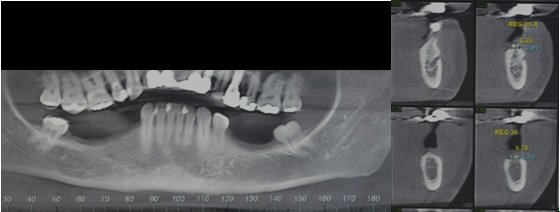

Para evitar riscos maiores é necessário, sempre que possível, obter uma tomografia computadorizada com um software específico para Implantodontia no planejamento inicial desses casos, minimizando o risco de lesão de nervo e orientando a posição tridimensional exata do feixe em relação à mandíbula, evitando assim o risco de remover osso sem necessidade.

- Analise radiográfica: rx panorâmico, rx periapical e tomografia computadorizada da região e se necessário prototipagem.

Depois de fazermos um planejamento detalhado na tomografia e modelo de estudo ou protótipos da mandíbula obtidos através da tomografia computadorizada, como tamanho e numero dos implantes, confeccionamos um guia cirúrgico em acrílico e marcando com precisão a localização dos implantes a serem instalados. Fig. 1 e 2